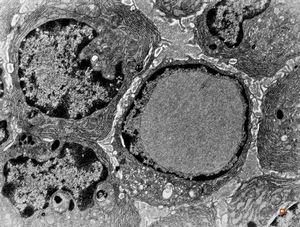

M,39y. | mitosis - chromophobic pituitary adenoma

M,62y. | mitosis - plasmocytoma

F,35y. | mitosis - intestine, celiakia

M,4y. | mitosis - retroperitoneal neuroblastoma

M,59y. | mitosis - angiomatous tumor, Kaposi sarcoma v.s.